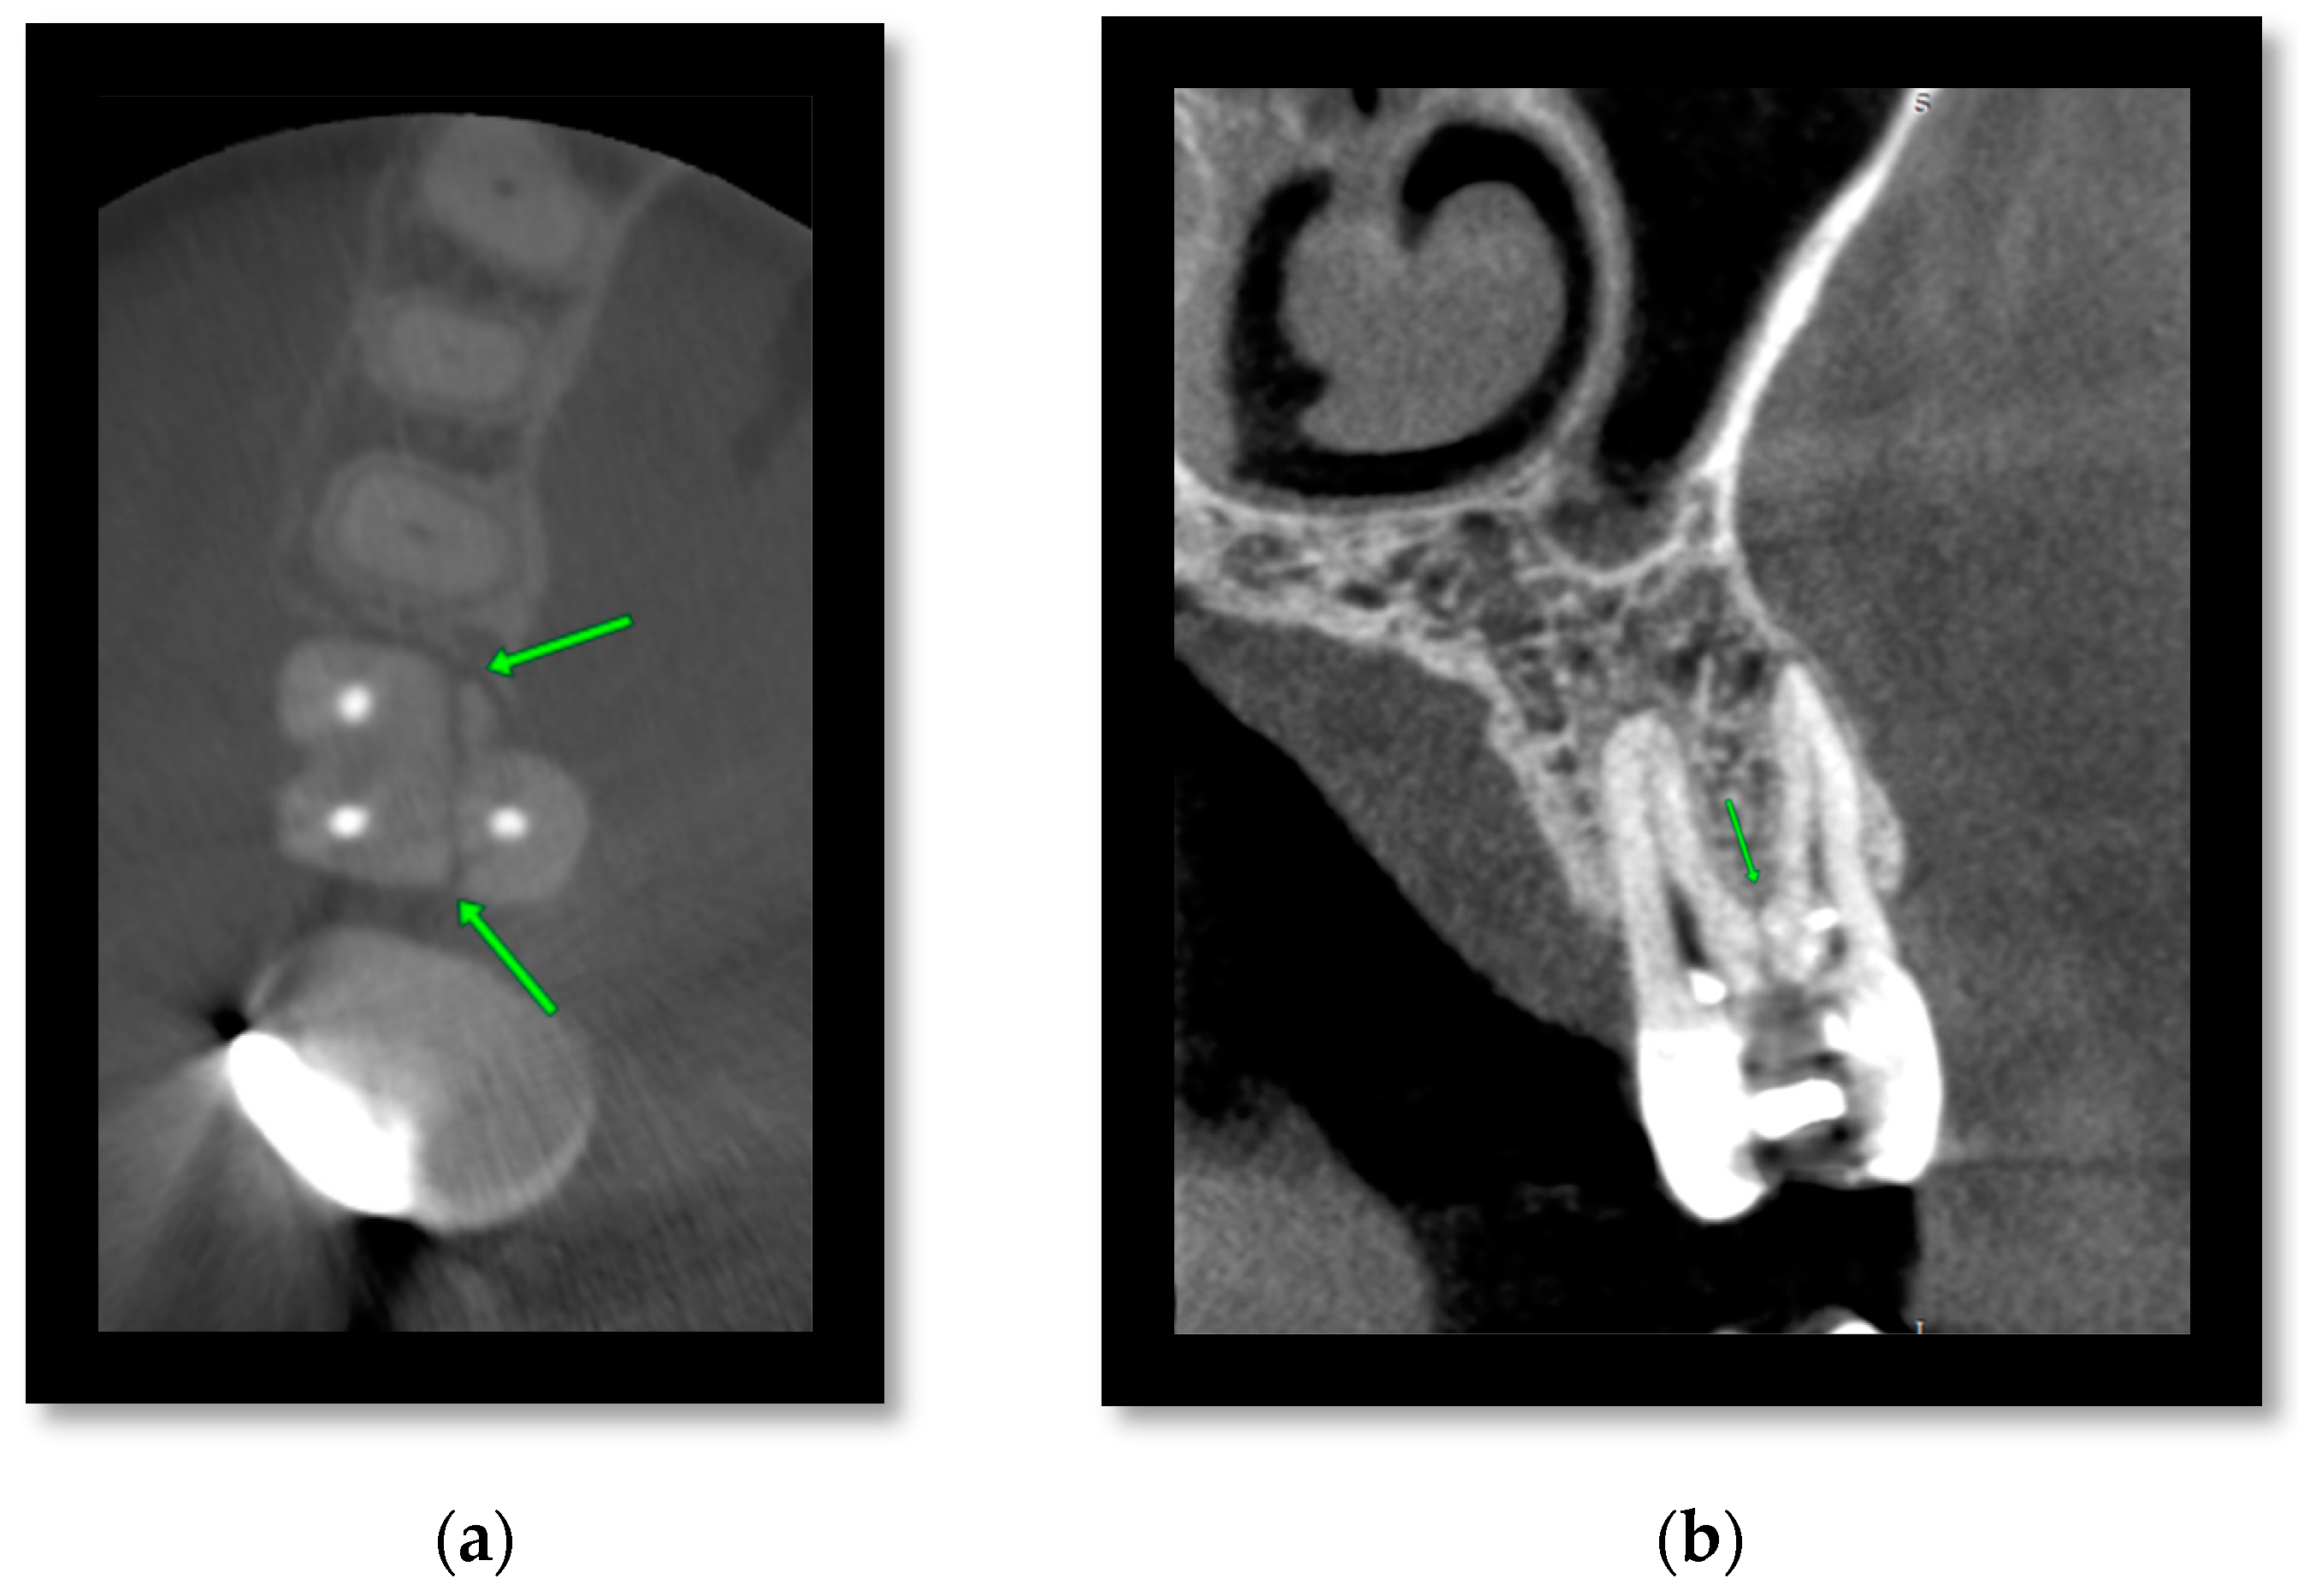

Figure 3 shows plain radiographs and CBCT images of a patient presenting with an infection following open reduction and internal fixation of a left angle of mandible fracture. Cross-sectional imaging in this case was able to confirm the suspicion of non-union on the plain film, as well as the lingual bone loss and periapical area associated with the LL7 apices, suggesting a loss of vitality in that tooth.

Figure 3.

(a) PA mandible and OPG and (b) sagittal, coronal, and axial slices demonstrating non-union of a left angle of mandible fracture. CBCT better visualizes the area of non-union and the lingual bone loss around the LL7 tooth (see arrow).

Figure 4 shows 2D images taken immediately post-operatively and CBCT images of the same patient at 24 months. The CBCT in this case can better visualise the position of the metalwork in relation to teeth and the inferior dental nerve. This added information can help inform decisions to remove metal work in patients with complications of nerve paraesthesia or non-vital teeth.

Figure 4.

(a) PA mandible and OPG and (b) axial, sagittal, coronal reformats, and a 3D reconstructed image. CBCT can better visualize the position of metalwork in relation to teeth and the inferior dental nerve and thus help inform decisions on metalwork removal.